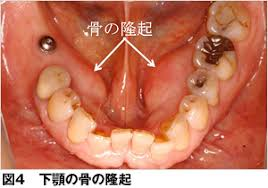

睡眠中に行う食いしばりは、起きているときの何倍もの力で噛んでいることが分かっています。毎晩、長時間にわたり上下の歯をこすり合わせていると、歯が削れてしまったり、歯が欠けたり、最悪の場合歯が折れてしまったりしてしまいます。歯が損傷されなくても歯を支えている歯根膜と呼ばれる感覚受容体が炎症を起こし歯の痛みとして感じることもあります。また、噛むことに使用する、咬筋とよばれる筋肉の炎症による痛みや、顎関節にかかる負担による顎関節症の誘発などもあります。人の組織は力がかかるところが発達してしまう傾向があります。いわゆる「えら」がはった顔貌の原因にもなってしまいます。口の中に下顎隆起とよばれる骨の塊ができてしまうこともあります。